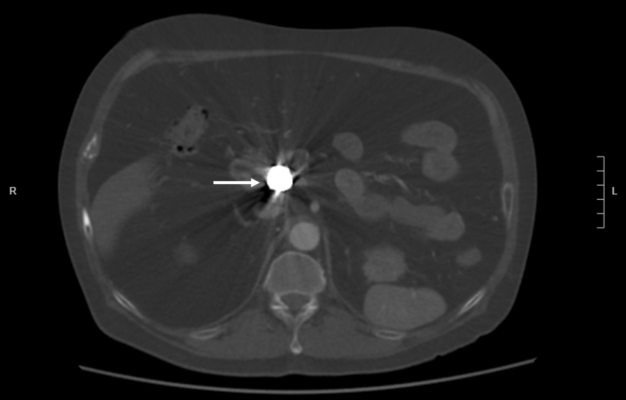

Recent CT imaging showed hypodense artefact over L1 on DXA image as a platinum-containing stent placed for a gastroduodenal artery aneurysm at L1 level

Dual-energy X-ray absorptiometry (DXA) is the gold standard for measuring bone mineral density (BMD). While most exogenous materials (e.g., calcification, standard surgical hardware) present as hyperdense artifacts that falsely elevate BMD, certain high-density materials and lytic pathologies can manifest as “hypodense” artifacts (the “black hole” effect), leading to diagnostic challenges. A 47-year-old male with metastatic renal cell carcinoma (mRCC) on the tyrosine kinase inhibitor axitinib was referred for DXA following multiple atraumatic rib fractures. DXA imaging of the lumbar spine revealed a focal hypodense artifact over L1 (Fig 1A). Recent CT imaging for correlation identified this as a platinum-containing stent placed for a gastroduodenal artery aneurysm (Fig 1B). Consequently, L1 was excluded from the Z-score calculation to prevent inaccurate assessment. Additionally, a hypodense region was noted in the left proximal femur (Fig 2A), which matched a known lytic bone metastasis with cortical disruption previously seen on CT (Fig 2B). This case illustrates that high-atomic-number metals—such as platinum, tantalum, or lead—can paradoxicaly cause “black holes” on DXA because their extreme attenuation exceeds the software’s threshold for bone, causing it to incorrectly subtract the area as background or soft tissue. In this patient, the clinical picture was further complicated by lytic metastases from mRCC, which also produce focal hypodensity. Clinicians must maintain a high index of suspicion when encountering hypodense artifacts on DXA. Accurate interpretation requires correlation with anatomical imaging (such as radiographs, CT) and clinical history. Known causes of hypodense artifacts include lytic bone lesions, laminectomy sites, high-density metals (platinum, tantalum), and spina bifida.